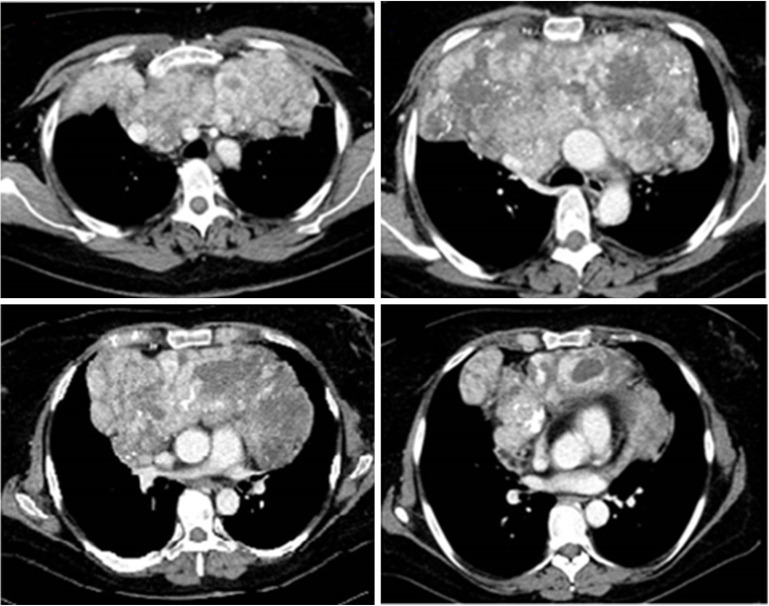

Case description: A 70-year-old patient with type-A thymoma underwent a via sternotomy thymectomy with an end-to-end caval anastomosis and an end-to-side anastomosis with the left brachiocephalic trunk by prosthesis. A 52-year-old patient with malignant peripheral nerve sheath tumor of left sternocleidomastoid muscle underwent surgical excision and chest wall reconstruction by Teflon prosthesis and pedicled flap from the rectus abdominis. A 41-year-old woman diagnosed with monophasic synovial sarcoma of the anterior mediastinum. After chemotherapy without benefit, she underwent debulking surgery with excision of this huge mass and right phrenic nerve reconstruction by neural graft from the contralateral phrenic nerve. A 23-year-old woman affected by myasthenia gravis (MG) with a type-B3 thymoma diagnosis. After chemotherapy without benefit, she underwent a thymectomy and left pneumectomy with reconstruction of the superior vena cava (SVC).